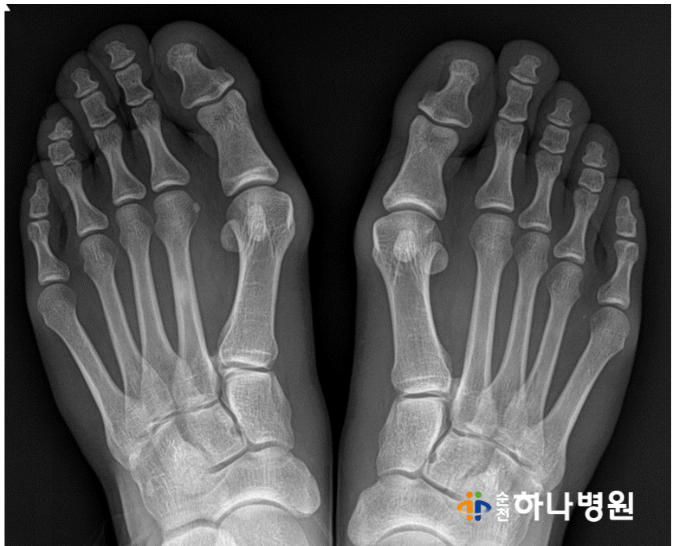

x-ray와 각도를 확인 한 결과

우측 ( 무지외반각도 31' / 제1-2 중족골간각도 16' )

좌측 ( 무지외반각도 25' / 제1-2 중족골간각도 16' )

양쪽 모두 '중등도 변형'을 나타내고 있는 상태!!

사진 상으로 양측 모두 엄지발가락이 두번째 발가락을

밀어 내고 있고, 제 1중족골두가 툭 튀어 나와있는 모습이

뚜렷했습니다.